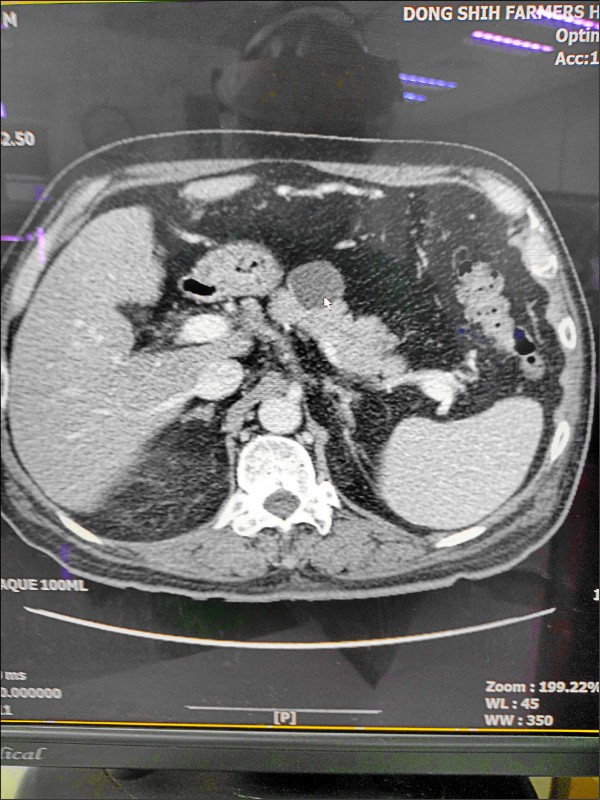

在他的胰臟體部發現1顆約2.5公分大的腫瘤,電腦斷層檢查高度懷疑是「胰臟囊腺腫瘤」(見下圖箭頭處),沒有淋巴結和遠處轉移,以外科手術切除,病理報告顯示為「黏液性囊狀腫瘤」,病人術後恢復良好。